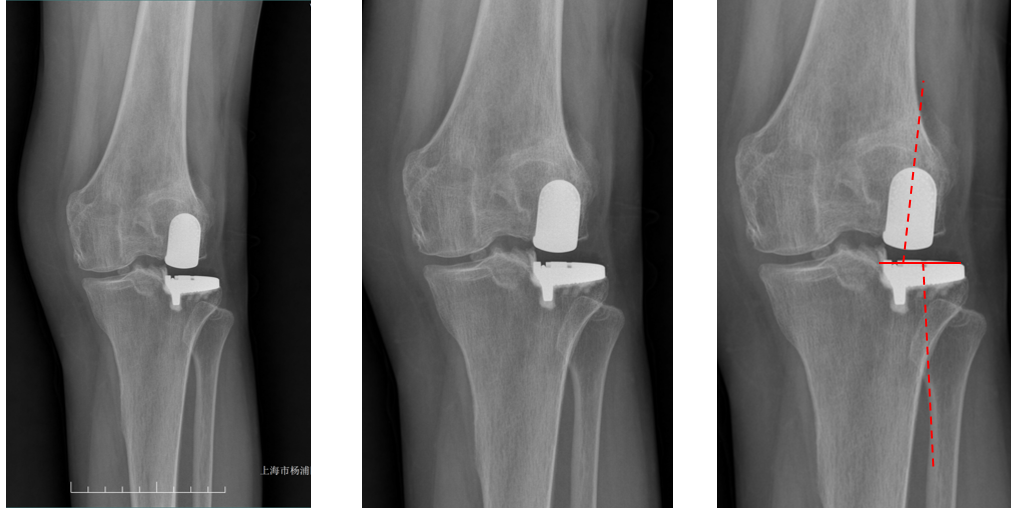

正位片标准胫骨和股骨假体位置

AP位假体位置:胫骨假体无内外翻,内侧缘超出胫骨平台内侧缘1mm; 股骨假体长轴与胫骨假体垂直,中线一致。

侧位片标准胫骨和股骨假体位置

侧位片假体位置:胫骨假体后倾3°,与胫骨平台前后缘齐平,股骨假体后倾40°,假体后缘与股骨后髁齐平。

胫骨假体厚度合适

胫骨垫片厚度合适:术前内翻畸形基本矫正,残留2-3°内翻。

股骨假体偏内放置,胫骨假体偏大

AP位胫骨与股骨假体位置:胫骨假体内侧悬挂>2mm,股骨假体中轴线与胫骨假体中线不一致,偏内侧。

股骨假体偏大且过度屈曲

侧位片假体位置:股骨假体后倾45°,假体后缘超出股骨后髁3mm, 胫骨假体后倾3°,与胫骨平台前后缘齐平。

AP位假体位置:胫骨假体外翻3°,内旋10°,外侧缘与胫骨平台外侧缘齐平; 股骨假体长轴与胫骨假体垂直,中线一致。

侧位片假体位置:胫骨假体后倾5°,与胫骨平台前后缘齐平,股骨假体后倾35°,假体后缘与股骨后髁齐平。